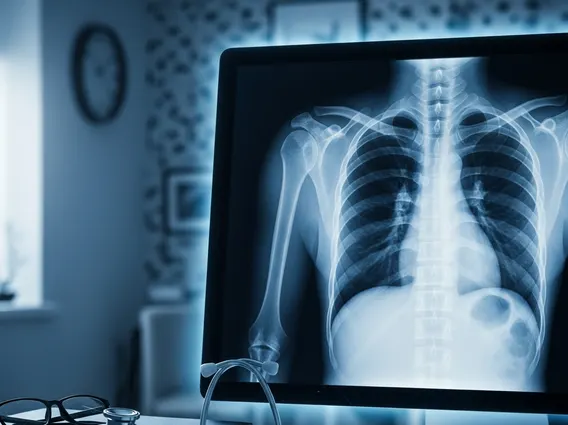

Chest X Ray

A Chest X Ray is a common imaging test that uses a small amount of radiation to create pictures of the chest, including the heart, lungs, blood vessels, airways, and the bones of the chest and spine. It’s a quick and non-invasive way for doctors to assess the health of these vital organs and structures.

A Chest X Ray, also known as a chest radiograph, is a fundamental diagnostic tool in medicine. It is an imaging technique that utilizes X-rays to generate two-dimensional images of the organs and structures inside the chest cavity. This includes the lungs, heart, large blood vessels, diaphragm, and the bones of the chest wall and spine. The primary purpose of understanding what is Chest X Ray is to help physicians detect, diagnose, and monitor various medical conditions affecting these areas, providing crucial insights into a patient’s health without invasive procedures.

Understanding how does a chest x-ray work involves grasping the principles of radiation. During the procedure, a machine sends a controlled beam of X-rays through the patient’s chest. Different tissues absorb X-rays at varying rates. For instance, dense structures like bones absorb more X-rays and appear white on the image. Soft tissues such as the lungs, which are filled with air, absorb fewer X-rays and appear darker. The X-rays that pass through the body are captured by a special detector, either a photographic film or a digital sensor, which then creates the visual image. This rapid process typically takes only a few seconds.

The process of interpreting chest x-ray results is performed by a radiologist, a medical doctor specializing in interpreting medical images. The radiologist examines the images for any abnormalities in the size, shape, and position of the heart, lungs, and other structures. They look for signs of infection, inflammation, fluid accumulation, tumors, fractures, or other indicators of disease. For example, pneumonia might appear as white patches (infiltrates) in the lungs, while an enlarged heart could suggest heart failure.